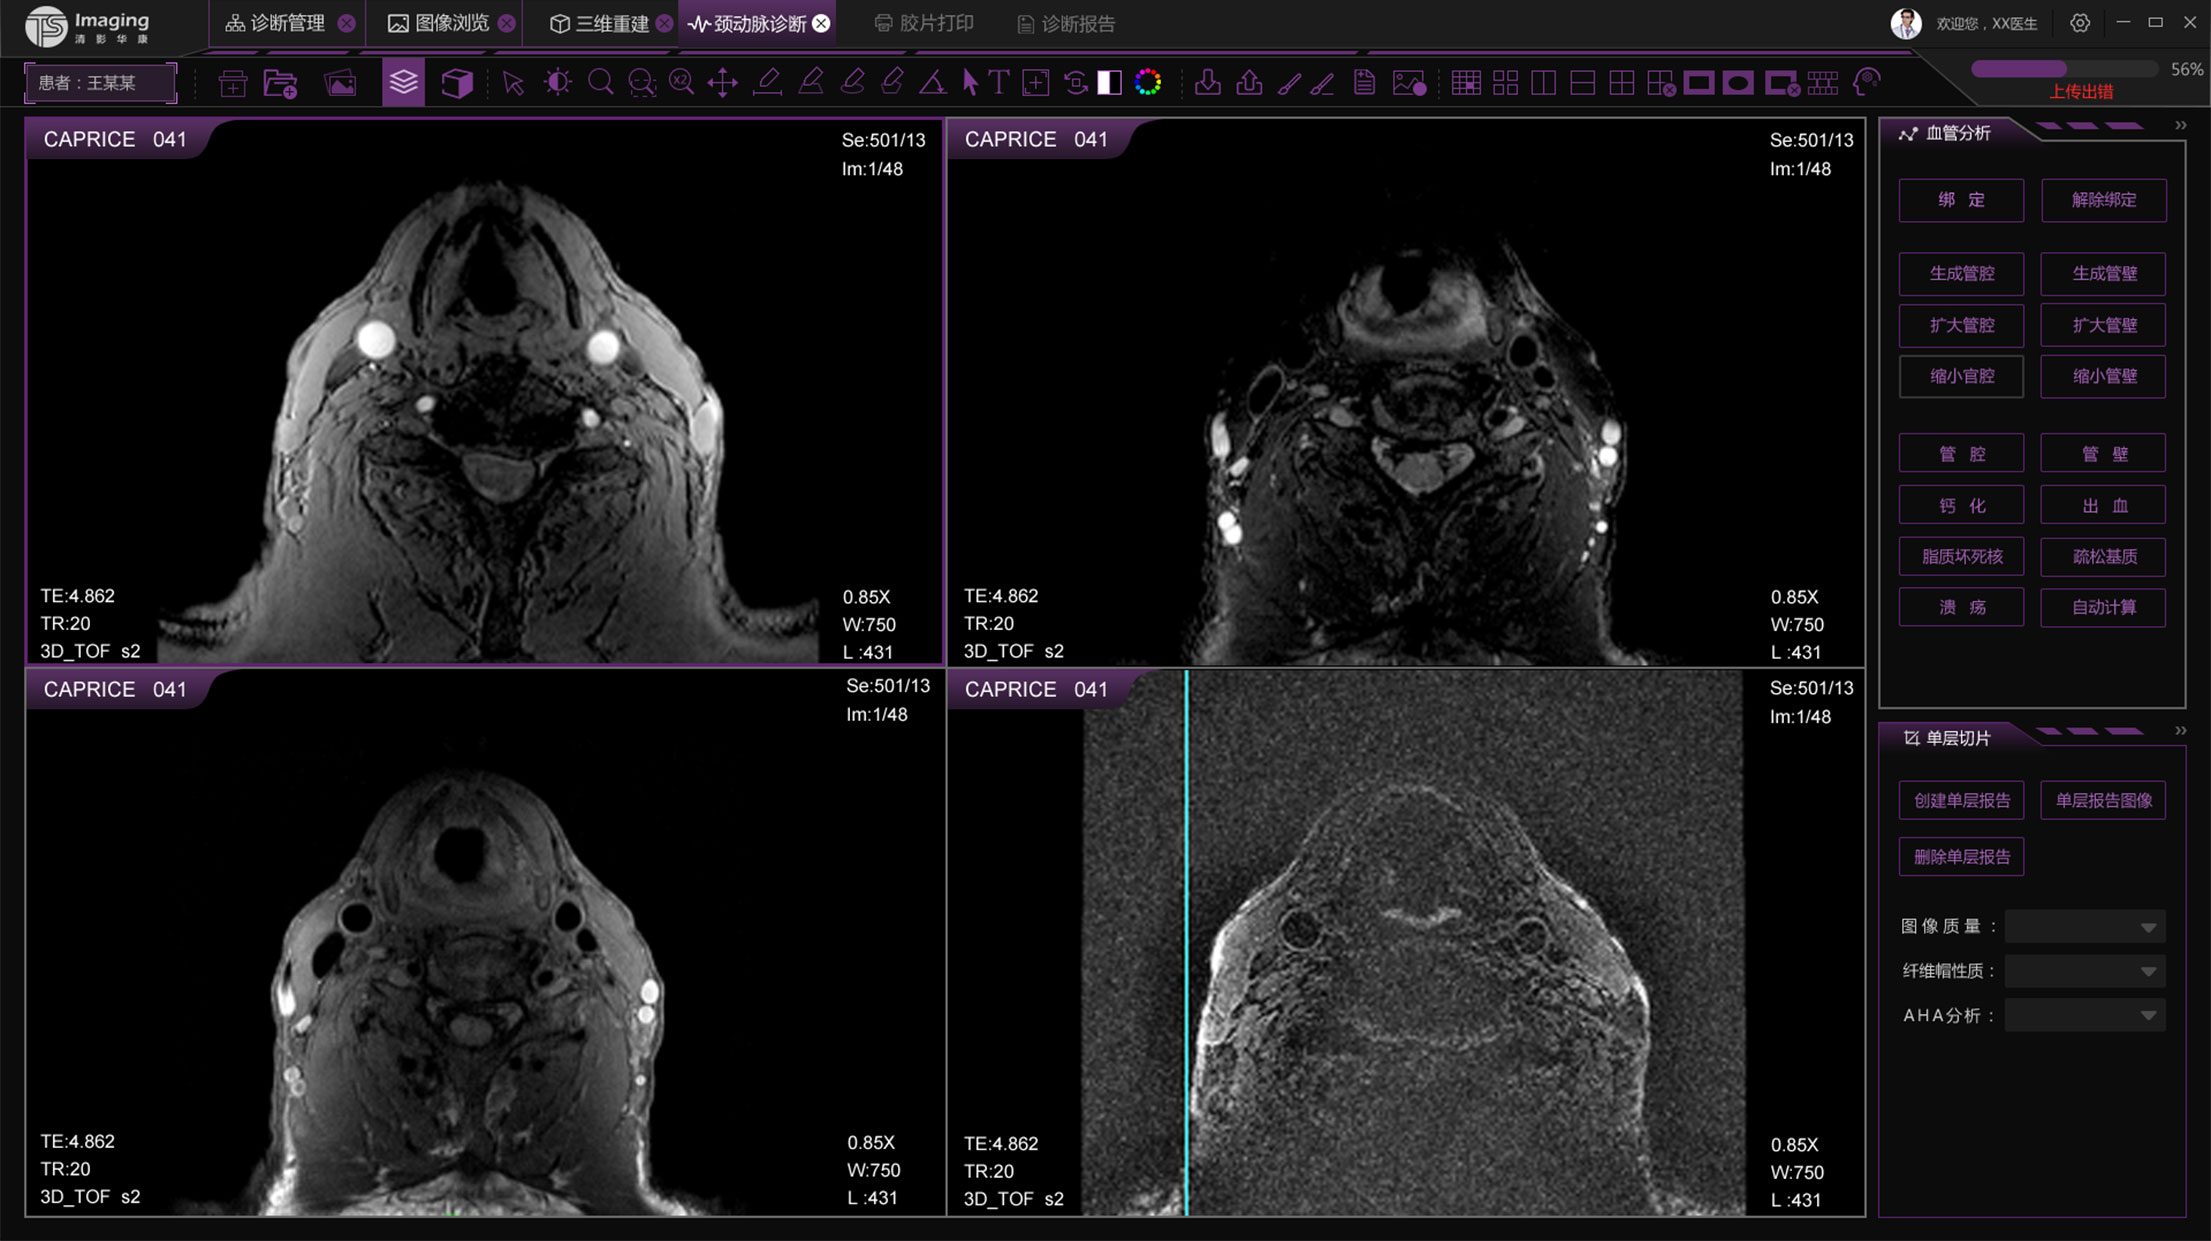

頸動(dòng)脈診斷頁面

頸動(dòng)脈診斷頁面整體布局和三維重建比較相似,最大的區(qū)別是右側(cè)的操作區(qū)域,血管分析都為按鍵操作,通過間隔的大小分成三部分。單層切片除了按鍵還有下拉菜單的操作。